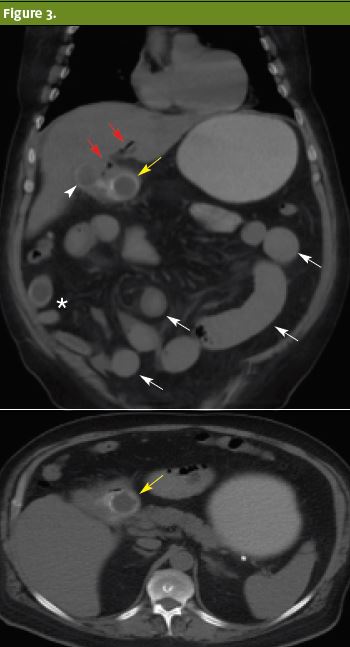

Surgery was consulted for gallstone ileus with distal jejunal obstruction (Figure 2, Figure 3). Patient was reexamined by the surgery team, who noted abdominal distension and guarding. A nasogastric tube was placed, and patient was taken to the operating room with a preoperative diagnosis of gallstone ileus, gastric outlet obstruction, jejunal partial obstruction, and cholecystoduodenal fistula.

Figure 3. Isotropic coronal (a) and axial (b) noncontrast CT of the abdomen. Multiple hypodense calculi with egg-shell calcifications are visualized in the gallbladder (arrowhead), duodenum (white hollow arrows) and small bowel (asterisk). A duodenal biliary calculus (hollow arrow), pneumobilia (black arrows) and dilated bowel loops (white solid arrows) are consistent with the Rigler’s triad.